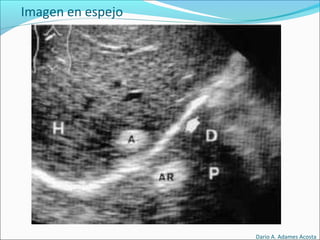

Imagen en espejo: Distorsión causada por rebote de haz

entre 2 elementos muy ecogénicos

Imagen en espejo

• #47 ARTEFACTOS Reverberaciones Se producen cuando el haz de ultrasonidos incide sobre una interfase que separa dos medios de muy diferente impedancia acústica, como por ejemplo entre un sólido ecogénico y gas en el tubo digestivo o entre sólido y hueso. REFUERZO ACUSTICO POsTERIOR Se produce cuando el ultrasonido atraviesa un medio sin interfases en su interior y pasa a un medio sólido ecogénico. Es casi característica exclusiva de imágenes quísticas en el seno de estructuras sólidas. quiste renal en el que se aprecia un importante refuerzo acústico posterior SOMBRA ACÚSTICA Se produce cuando el ultrasonido choca con una interfase muy ecogénica y no puede atravesarla no detectándose ninguna imagen detrás de esta interfase tan ecogénica. Es muy característico de las litiasis biliares y renales y de las calcificaciones musculares. litiasis biliar , observamos como la señal hiperecogénica que corresponde a la litiasis deja una sombra COLA DE COMETA Ocurre cuando el haz de ultrasonidos choca contra una interfase estrecha y muy ecogénica apareciendo detrás de esta interfase una serie de ecos lineales. Es muy característico de los adenomiomas de pared vesical, cuerpos extraños muy ecogénicos y también pequeñas burbujas de aire en el seno de un medio sólido. adenomiomatosis de la pared de la vesícula biliar IMAGEN EN ESPEJO Se produce cuando una interfase muy ecogénica se encuentra delante de otra imagen curva tan ecogénica como ella produciéndose una sobra acústica posterior. hemangioma hepático cerca del diafragma que da una imagen igual extradiafragmática que es la imagen en espejo ANISOTROPIA Es la propiedad que tienen algunos tejidos de variar su ecogenicididad dependiendo del ángulo de incidencia del haz ultrasónico sobre ellos. La estructura anisotrópica por excelencia es el tendón. inserción tibial del tendón rotuliano y vemos que si la sonda no esta perpendicular nos da una falsa imagen de tendinitis, ya que se ve el tendón hipoecogénico